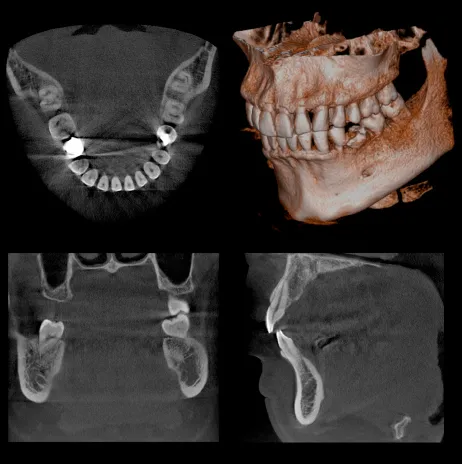

CTを導入しています

当院ではまだまだ個人の歯科医院での普及率が低い、CT(コンピュータ断層撮影機)を導入いたしました。

通常のX線撮影では、歯やアゴの骨の状態を二次元でしか確認できないため、色々な病状(歯の根の病気や歯周病の病状)を見落としてしまう可能性は否定でき ません。CTを撮影することによって、あらゆる方向から三次元で歯やアゴ骨の状態を確認可能なため、詳細な診断が可能になります。

撮影時間も9.4秒と極めて短く、放射線の被曝量は、医科用CT撮影(頭部)の1/77~1/23以下です。

限られた病変(歯の神経の治療、歯周病の治療、親知らずの抜歯など)においては保険適用での撮影が可能です。

また、インプラントの手術をする際には、アゴの骨の状態を診査するにはCT撮影が必要であり、その後の定期診査にも非常に有効です。

医科用CT撮影に比べると少ないながらも、被爆のデメリットもありますので、必要に応じて使用し、診査・診断に大いに役立てていきたいと思います。